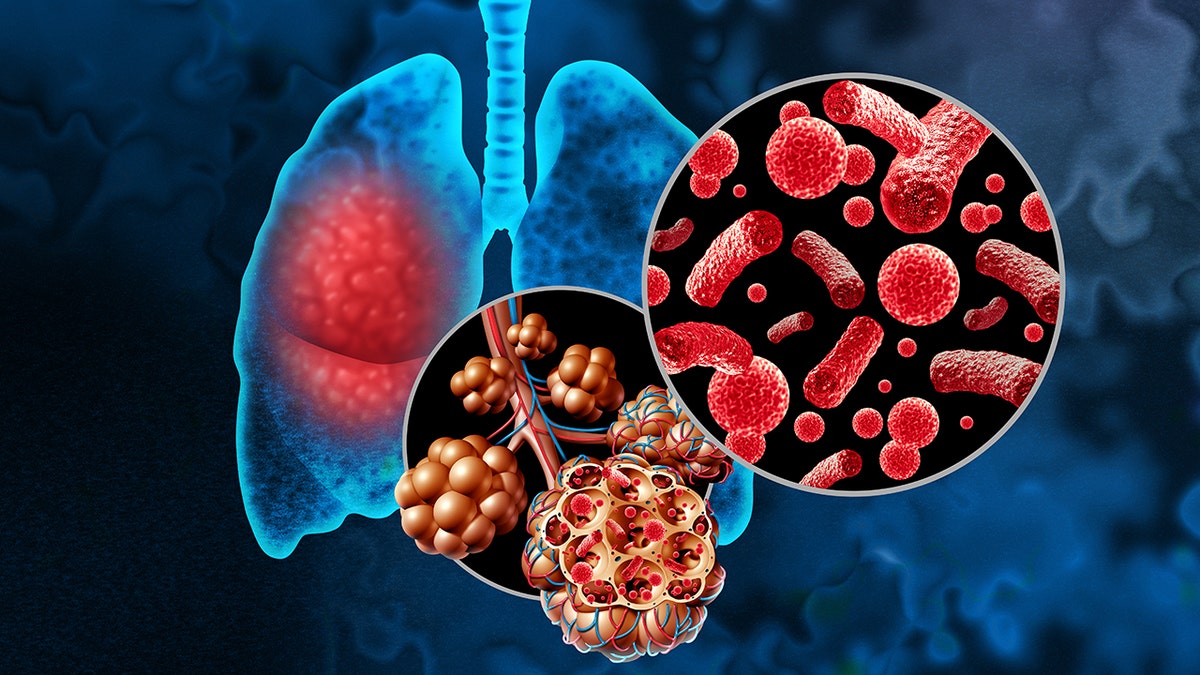

Pneumonia is defined by Cleveland Clinic as an infection in the lungs caused by bacteria, viruses or fungi.

This can cause the lung tissue to swell and create a buildup of fluid or pus in the lungs.

Bilaterial pneumonia, also known as double pneumonia, occurs in both lungs at the same time.

Pneumonia is defined as an infection in the lungs caused by bacteria, viruses or fungi. (iStock)